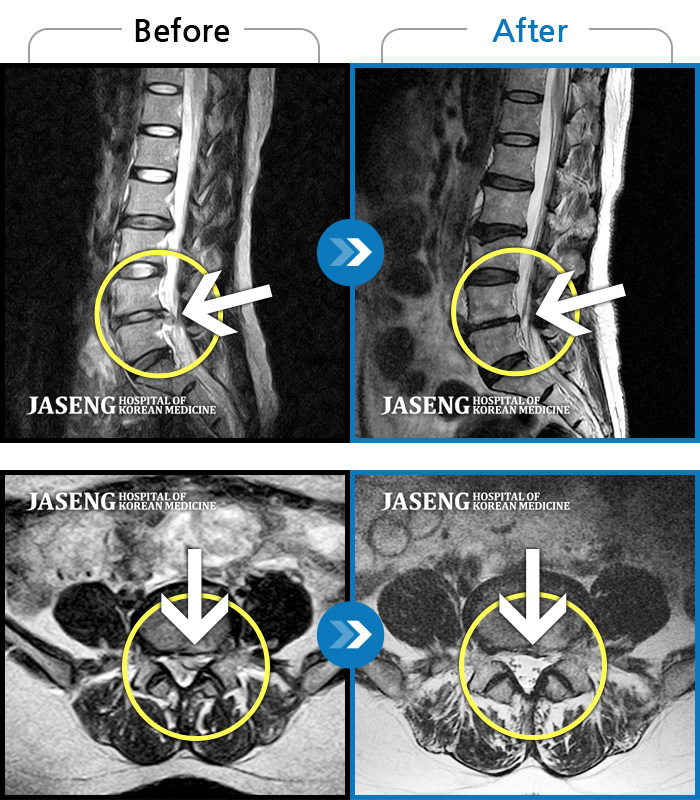

허리디스크

수원 · 김태성 원장

허리 통증과 우측 고관절~하지방사통이 심하여 활동하기 힘든 상태

촬영시기

2021.03.04 ~ 2021.10.06

2022.03.25